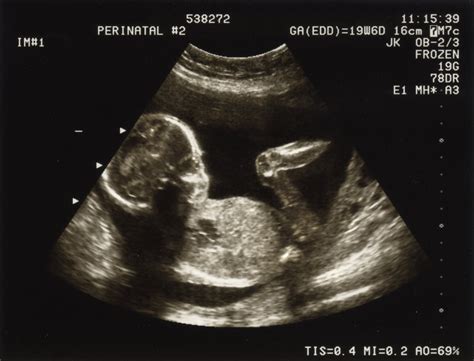

Diagnosticul se bazează pe simptome și investigații medicale, inclusiv examen clinic, ecografie transvaginală și analize de sânge (nivel HCG). Gestionarea poate fi naturală (expectativă), medicamentoasă sau chirurgicală, în funcție de stadiul sarcinii și starea pacientei.